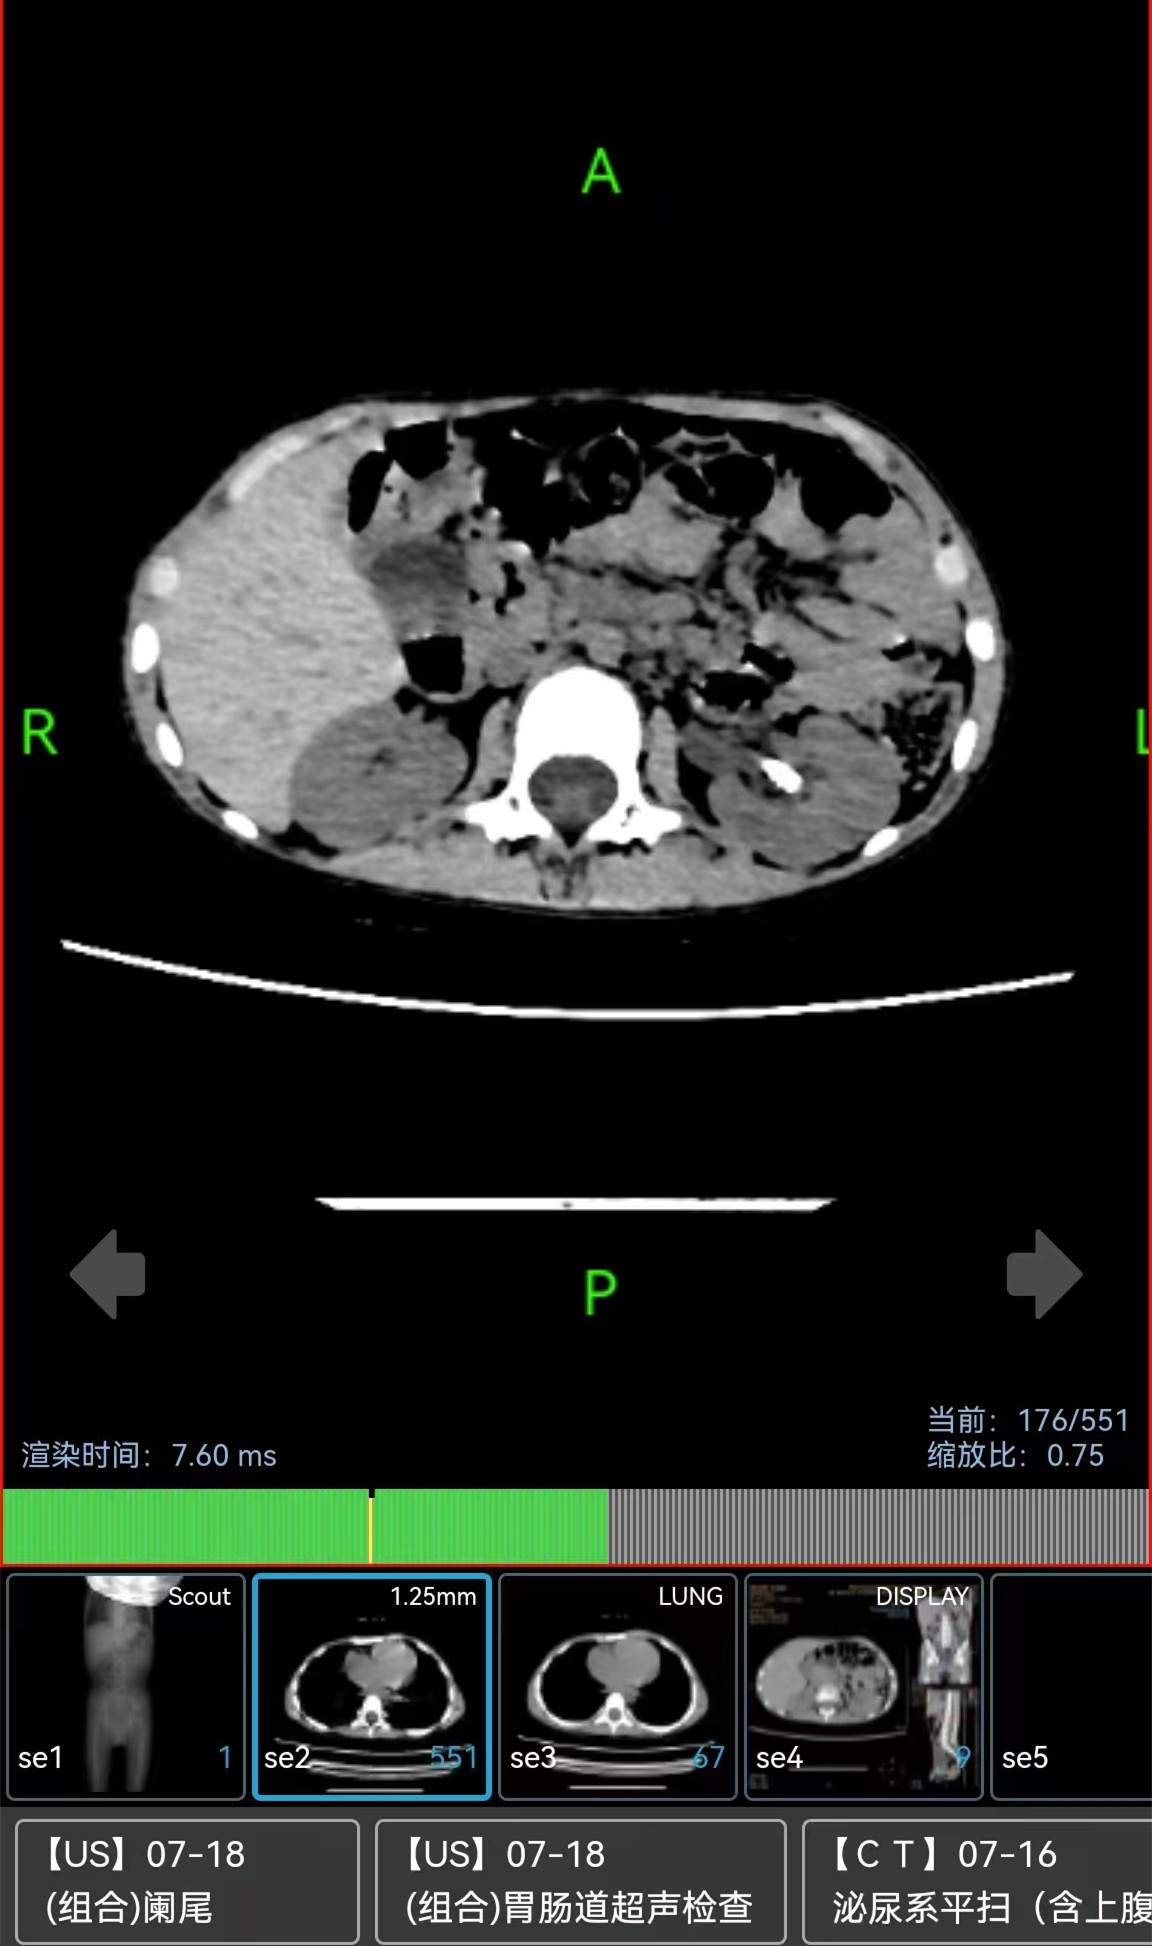

▲术后CT图片显示左肾结石已消失,右肾轻度积水